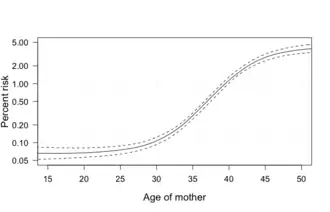

The parents of the affected individual are usually genetically normal.[15] The probability increases from less than 0.1% in 20-year-old mothers to 3% in those of age 45.[4] The extra chromosome is provided at conception as the egg and sperm combine.[16] A very small percentage of 1-2% gets the additional chromosome in the embryo stage and it only impacts some of the cells in the body; this is known as Mosaic Down syndrome.[17][18] Usually, babies get 23 chromosomes from each parent for a total of 46, whereas in Down syndrome, a third 21st chromosome is attached.[18] It is believed to occur by chance, with no known behavioral activity or environmental factor that changes the probability.[2] Down syndrome can be identified during pregnancy by prenatal screening, followed by diagnostic testing, or after birth by direct observation and genetic testing.[6] Since the introduction of screening, Down syndrome pregnancies are often aborted (rates varying from 50 to 85% depending on maternal age, gestational age, and maternal race/ethnicity).[19][20][21]

Maternal age affects the chances of having a pregnancy with Down syndrome.[4] At age 20, the chance is 1 in 1,441; at age 30, it is 1 in 959; at age 40, it is 1 in 84; and at age 50 it is 1 in 44.[4] Although the probability increases with maternal age, 70% of children with Down syndrome are born to women 35 years of age and younger, because younger people have more children.[4] The father's older age is also a risk factor in women older than 35, but not in women younger than 35, and may partly explain the increase in risk as women age.[135]